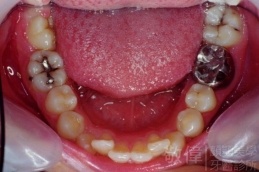

齒顏矯正/戽斗臉型 變身 大帥哥

矯正前-右   矯正前-正   矯正前-左

矯正後-右   矯正後-正   矯正後-左

矯正前-上   矯正前-下

矯正後-上   矯正後-下

<個案說明>

戽斗(學名第三級咬合 class III)矯正之後,戽斗的樣子就比較沒有了。最主要的改變是在牙齒的咬合。從側面比較,治療前、治療後的臉型 可更明顯看出來 戽斗的感覺 減少了很多。